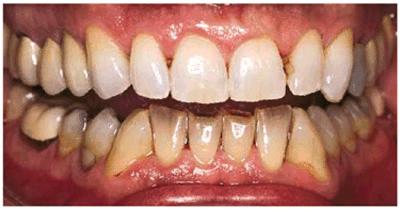

TETRACYCLINE STAINING

Tetracycline is considered one of the most difficult tooth stains to remove.

In-office bleaching is a possible treatment method but generally is

contraindicated due to the number of treatments required and the concurrent

high fee and patient discomfort. With the advent of at-home bleaching, these

tetracycline stains can be managed more easily.49,51,60 Treatment

times may vary from 2 months to 1 year (Figures 16-28A 16-28B 16-28C 16-29A 16-29B 16-30A 16-30B 16-31A, and 16-31B). Patients are seen monthly to

Figure 16-29A: Moderately tetracycline-stained teeth.

Figure 16-29B: In a research study, these teeth were bleached for 6 months nightly with a 10% carbamide peroxide. Not all results will be this good, especially if the discoloration is blue/gray or at the gingival third.

Figure 16-30A: Moderately tetracycline-stained teeth.

Figure 16-30B: After only 2 months of treatment, the results are satisfactory. Patients with tetracycline-stained teeth should commit to at least 2 months of treatment.